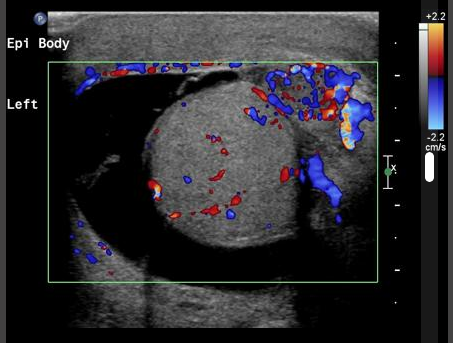

USS is especially useful in patients with sudden onset pain to assess for Testicular Torsion (no flow on colour doppler in many cases) and to assess for Epididymo-orchitis (increased flow in many cases)

Ultrasound 2 – Testicular Torsion may be suggested by reduced flow in testes demonstrated on colour doppler studies.